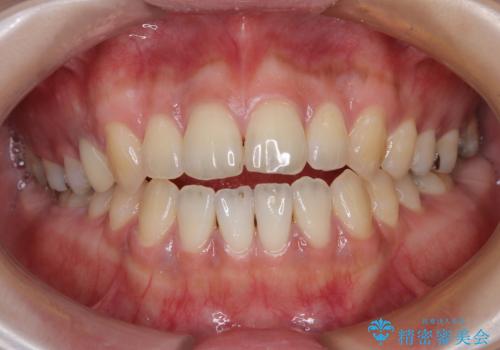

非接触の前歯と下顎のデコボコ ワイヤー装置による矯正治療

横顔の印象を変えたい ワイヤー装置での抜歯矯正